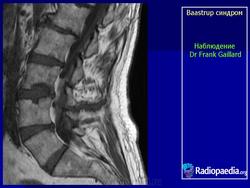

"Бааструпа (Baastrup) болезнь, osteochondrosis interspinalis, arthrosis interspinal, kissing spine, описана в 1932 г. Характеризуется наличием хронических воспалительных изменений в остистых отростках позвонков. Вследствие этого возникают длительно удерживающиеся боли в поясничном отделе позвоночника, особенно при чрезмерном изгибе его кзади или чрезмерной нагрузке (поднимание тяжестей), с местной болезненностью в области остистых отростков. На рентгенограмме видны расширенные остистые отростки со склеротическими краями, иногда на верхнем или нижнем крае отростка остеофиты, которые могут даже соприкасаться между собой. Этиология-врожденное, неправильное развитие остистых отростков поясничных позвонков; заболевание наблюдается в определенном возрасте (30-40 лет) и у людей определенных профессий (грузчики).

Следует учитывать и относительную частоту неоартроза между остистыми отростками - межостистый диартроз (Meyer Н., 1924), «целующиеся отростки» (BrailsfordJ., 1929; Baastrup С, 1933). Синдром Бааструпа может сопровождать межпозвонковый остеохондроз (Forrai J., Tannai J., 1962). Е.С.Заславский и соавт. (1973) среди больных поясничным остеохондрозом определяли клинические и рентгенологические признаки синдрома Бааструпа в 5,5%. Боли при данном синдроме по характеру тупые, ноющие, сверлящие. Они усиливаются после длительного сидения, переноски тяжестей, при разгибании туловища. Выявляются болезненность и ограничение подвижности позвоночника (особенно в позе разгибания) на уровне пострадавших двигательных сегментов, болезненность при пальпации соответствующих межостистых промежутков. При вызывании феномена вибрационной отдачи в области поясничных межостистых связок боли, как правило, не только усиливаются, но и иррадиируют в пределах скле-ротома: в крестец, ягодицу, бедро. Инфильтрация же 1-2 мл 1% раствора новокаина межостистого промежутка быстро снимает эти феномены. Синдром связывают с поясничным гиперлордозом, структуральным сколиозом, переломом и вывихом позвонков, деформирующим спондилезом с аномальным увеличением остистых отростков. С.А.Рейн-берг (1964) относил изменения остистых отростков при данном синдроме к явлениям патологической перестройки костной ткани, обусловленной нагрузками чрезмерной силы на задние отделы позвоночного столба. Согласно N.Fellmann (1964), формирование сустава между остистыми отростками проходит следующие стадии: межостистый остеосклероз, фасетирование и склероз, тяжелое артрози-рование, анкилоз.

Рисунок 1